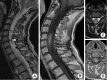

Methods: Forty-eight patients were treated for an intramedullary tumor between 2014 and 2020 at a single institution. Patients' files were retrospectively studied. We detailed clinical status according to neurological deficit and ambulatory ability using the modified McCormick Scale, radiological features like number of levels, associated syringomyelia, surgical technique with or without intraoperative electrophysiological monitoring, pathological findings, and postoperative outcome.

Results: The median age of this population was 43 years, including 5 patients under 18 years. The median delay before first neurosurgical contact was 3 months after the first clinical complaint. Treatment was gross total resection in 43.8%, subtotal resection in 50.0%, and biopsy in 6.2%. A laminectomy was performed for all the patients except 2 operated using the laminoplasty technique. Pathological findings were ependymoma in 43.8%, hemangioblastoma in 20.8%, and pilocytic astrocytoma in 10.4%. Six patients were reoperated for a tumor recurrence less than 2 years after the first surgical resection. One patient was reoperated for a postoperative cervical kyphosis.